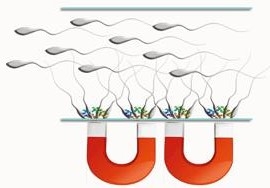

Техниката на магнитно клетъчно сепариране /MACS/

Публикувано на: 10.02.2013 Техниката на магнитно клетъчно сепариране /MACS/ оказва положителен ефект върху подвижността на сп...

ПовечеОтстраняване на ДНК фрагментирани сперматозоиди (MACS)

Публикувано на: 10.02.2013 Една от основните причини за неуспех при прилагане на АРТ процедурите са т.нар апоптични сперматозои...